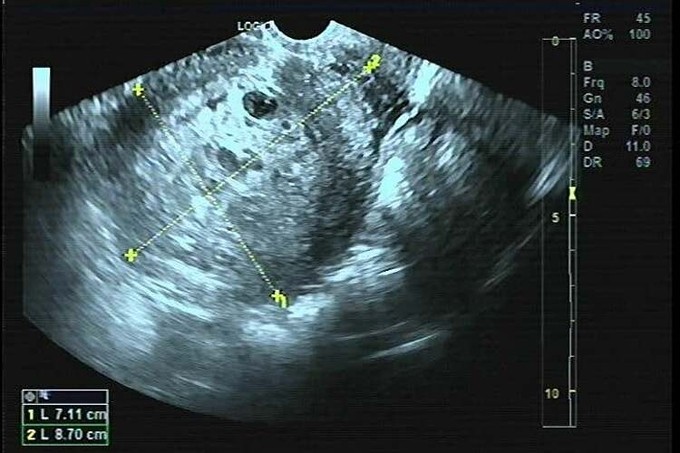

Hình ảnh siêu âm của bệnh nhân. Ảnh: Bệnh viện cung cấp

Bác sĩ khám ghi nhận âm đạo có nhiều máu đen, tử cung kích thước to hơn bình thường, hai phần phụ chưa sờ thấy khối bất thường. Bác sĩ Nguyễn Thị Hiền, chuyên Khoa Sản, chỉ định bệnh nhân thực hiện một số xét nghiệm như Beta-hCG, đông máu, tổng phân tích máu, siêu âm ổ bụng và siêu âm đầu dò. Kết quả xét nghiệm có nồng độ Beta-hCG máu tăng cao > 200.000 u/l.

Chửa trứng được chẩn đoán xác định chủ yếu dựa vào siêu âm và xét nghiệm nồng độ Beta- hCG. Với siêu âm, chửa trứng có thể được phát hiện rất sớm và dễ dàng, thường ở thai dưới 9 tuần.